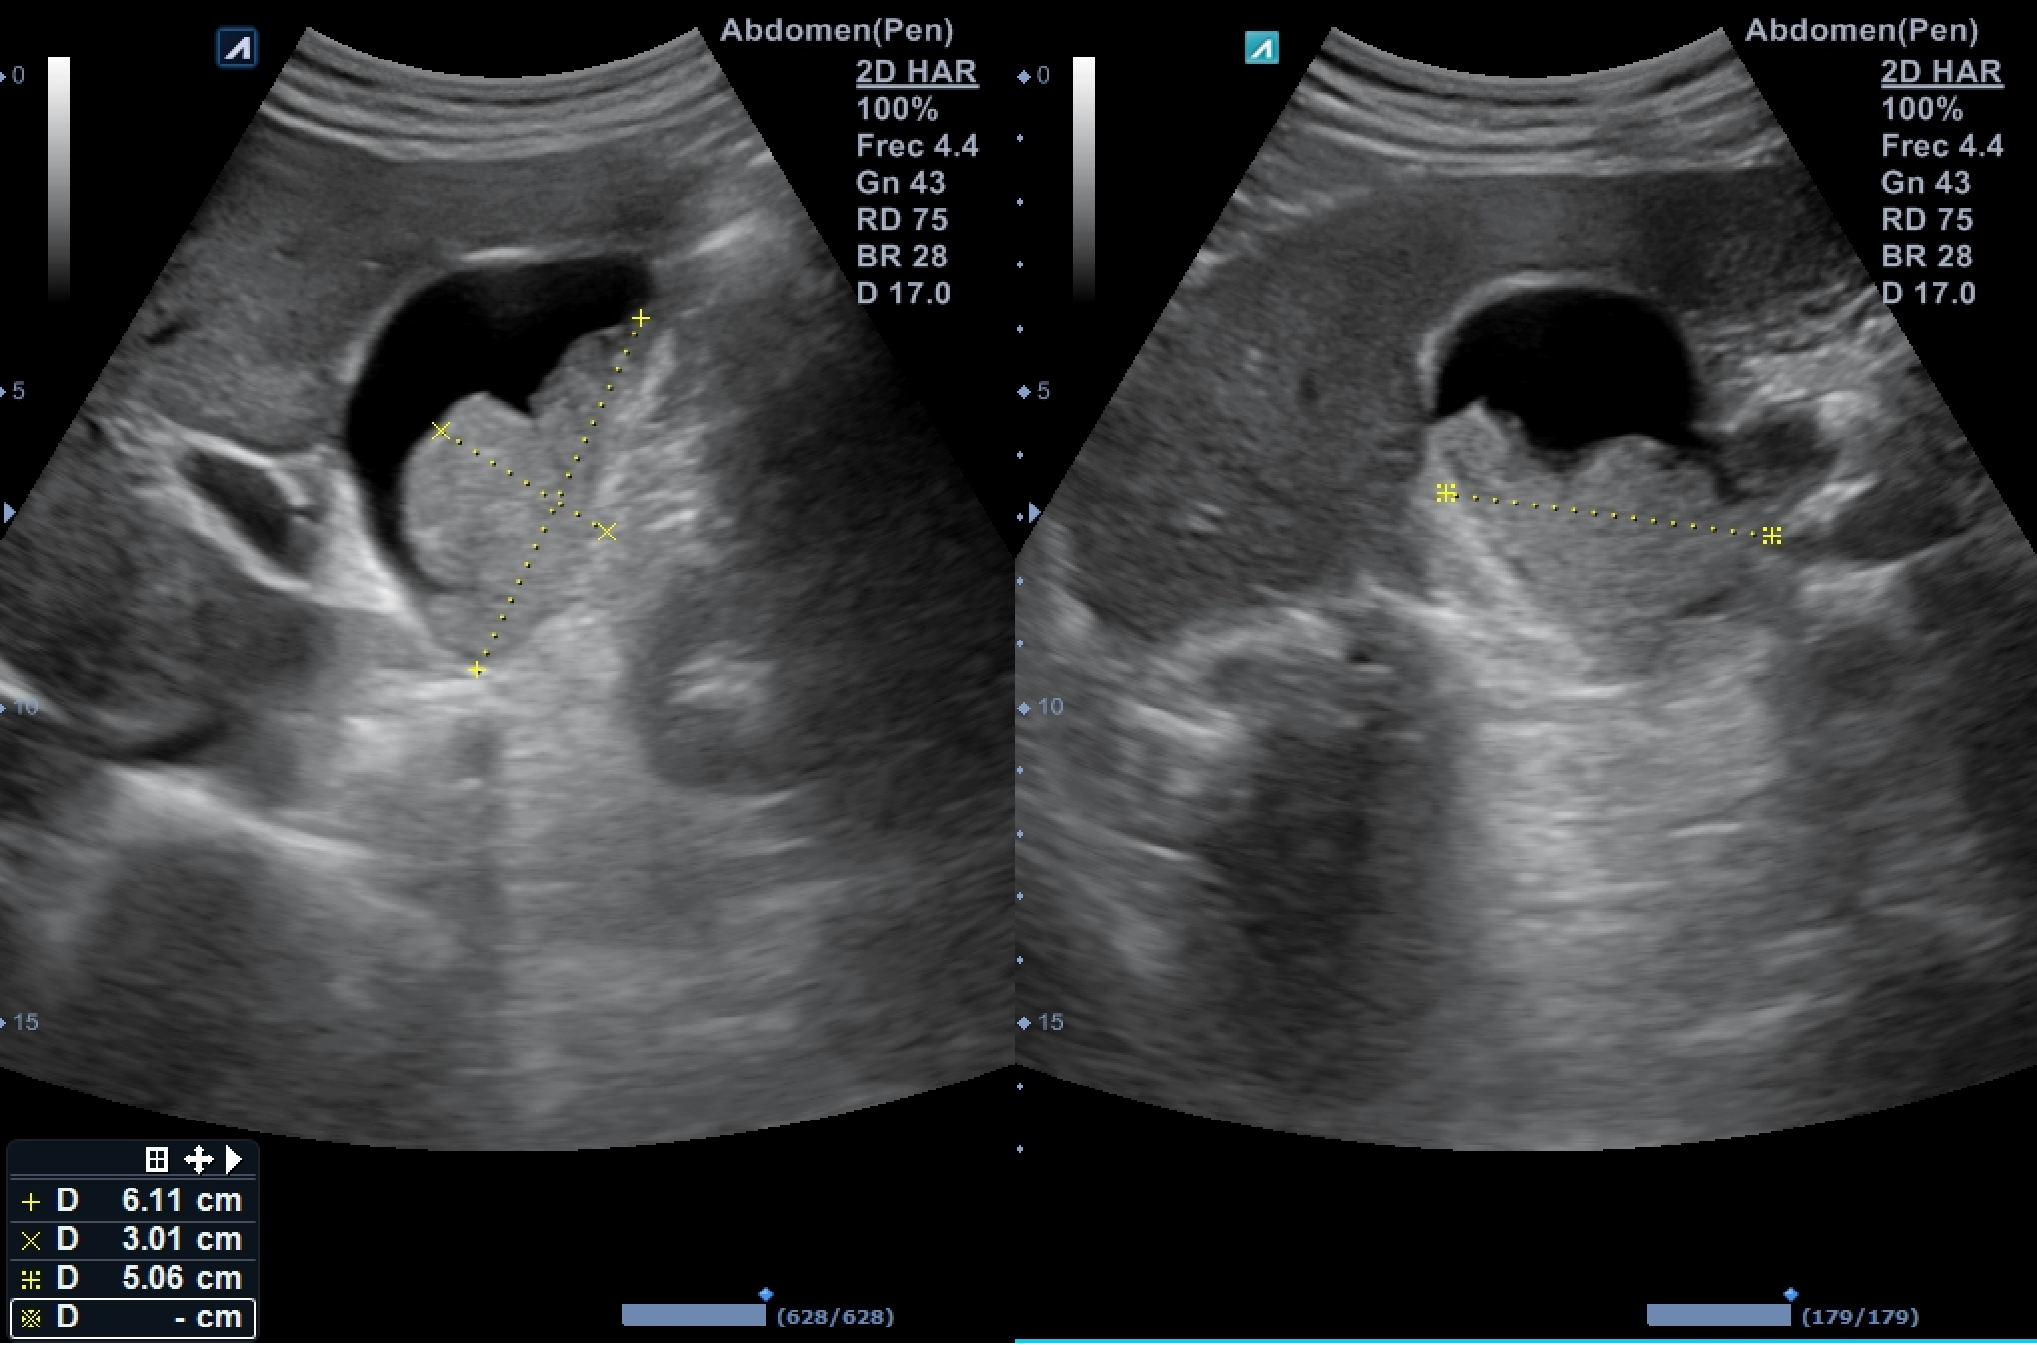

Ecografía abdominal dónde destaca vesícula biliar de pared fina (hasta 3,4 milímetros en su punto de mayor grosor) sin colecciones perivesiculares, que alberga en su interior imagen polilobulada sólida de efecto masa dependiente de su pared posterolateral e inferior que ocupa más de la mitad de la luz, sin captación de flujo Doppler, sugerente de polipoidea o tumoral, de unos 6 x 5 x 3 centímetros de dimensiones mayores.

Actualmente el paciente se encuentra en seguimiento por su médico de atención primaria dónde se realizan ecografías abdominales para vigilar el crecimiento de la imagen intravesicular que continúa aumentando de tamaño.